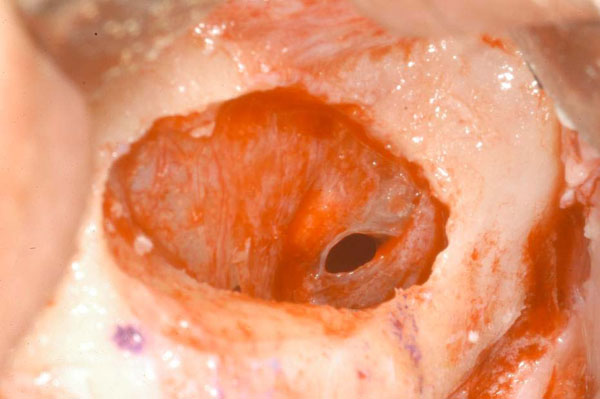

Fig. (4).

Double window design. AAA course remains covered by a bony wall as a protection from possible damages.